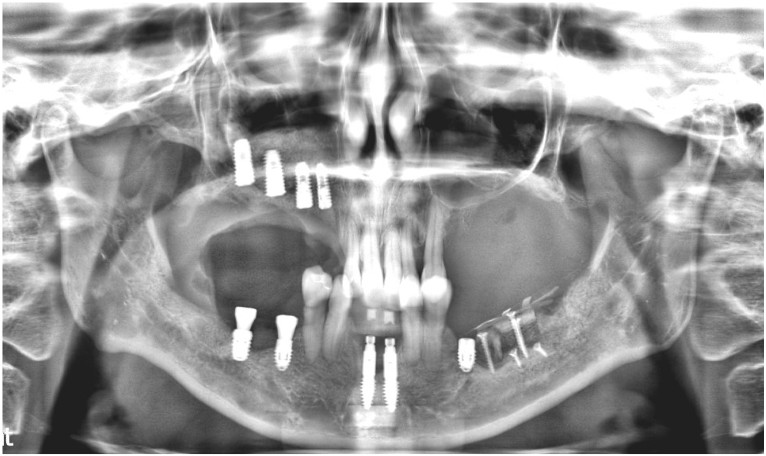

환자분께서는 2년 반쯤에

내원해 주셨던 적이 있으셨는데요.

위 사진은

그 당시 파노라마 사진으로

그때도 만성 치주염 진단을 받으셨지만

지속적인 치료와

관리가 잘되지 않아

현재 더 심해진 상태입니다.